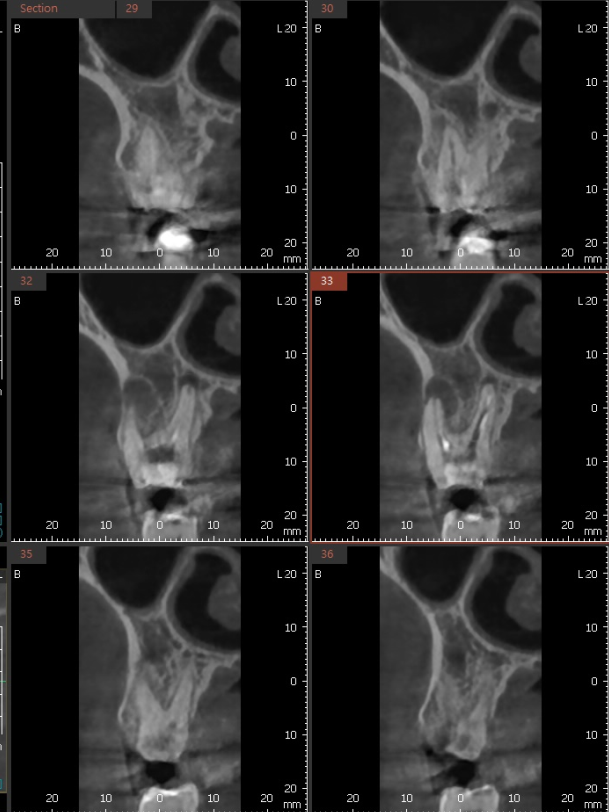

3D ct 등을 통해 정밀한 검사를 진행한 결과,

치아 뿌리 주변의 염증으로 한쪽 뼈를 녹였네요.

ct 상 한쪽 뼈만 녹아있는 상황이라

반대편 뼈에 기대해보면서

환자분은 뼈가 차고 있는지

지속 확인이 필요했습니다.

치료가 끝났어도 안심할 단계가 아니다.

6개월정도 더 지켜보자 말씀드렸죠.

염증이 남아있으면 제대로 뼈가 차지 않는대요.

깨끗하게 염증이 없어졌기 때문에

까맣게 녹아 버린 뼈가

다시 하얗게 채워진 모습을 볼 수있네요~